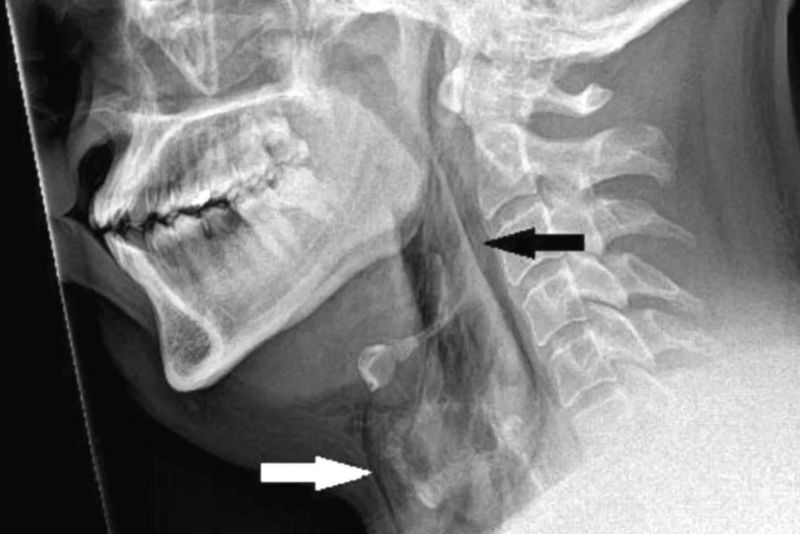

Yapılan taramalarda hastanın nefes borusunda 2 milimetrelik bir yırtık olduğu ortaya çıktı.

Doktorlar hastayı muayene için boynuna dokunduklarında bir çıtırtı sesi duymuş ve hastanın hareket kontrolünün olmadığını tespit etmişti.

Raporu hazırlayan Dr. Rasads Misirovs, "Burnu sıkışık ve ağzı kapalı bir şekilde hapşırırken soluk borusunda hızlı bir şekilde basınç oluşması nedeniyle soluk borusunun yırtıldığından şüpheleniyoruz" dedi ve bu risk nedeniyle, ağzı ve burnu kapatarak, hapşırmanın bastırılmaması konusunda uyardı.

Tıbbi adıyla "spontane trakeal perforasyon" olarak bilinen ani boğaz yırtılması nadir görülse de potansiyel olarak hayati tehlikeye yol açabilir.